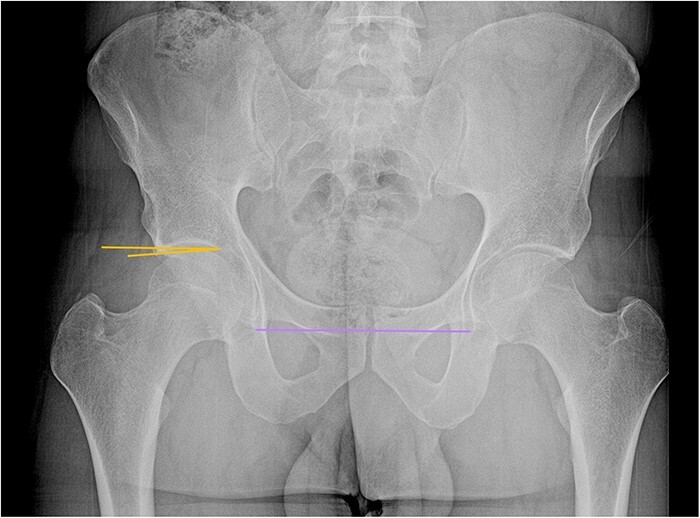

股髋臼撞击综合征(FAIS)是髋关节的一种常见疾病,可对关节造成严重损害,导致退变和骨关节炎。FAIS是股骨头颈交界处与髋臼缘之间的异常动态接触,由一个或两个部位的骨形态改变引起。撞击部位的重复性创伤会对髋臼唇、软骨唇交界处和关节软骨造成进行性损伤。基于患者症状、特定临床体征和影像学表现的正确诊断将指导治疗并最终保留原有髋关节。FAIS患者的常见症状包括疼痛、咔嗒声、卡住、屈曲、僵硬、让位和髋关节活动范围有限。具体的临床操作可以帮助诊断,如屈曲内收内旋和屈曲外展外旋试验。影像学诊断包括髋关节和骨盆的正交x线片,以及磁共振成像/磁共振关节成像。FAIS的初始治疗可以是保守治疗,包括物理治疗、关节内注射和活动调节。目前,首选的手术治疗包括髋关节镜检查,其目的是纠正骨骼异常,修复或重建唇部病变,并根据需要处理其他关节内和关节外的紊乱。

Femoroacetabular impingement syndrome (FAIS) is a common condition of the hip that can cause significant damage to the joint, leading to degeneration and osteoarthritis. FAIS constitutes an abnormal and dynamic contact between the femoral head-neck junction and the acetabular rim, resulting from altered bone morphology at one or both sites. Repetitive trauma at the site of impingement generates progressive damage to the acetabular labrum, chondrolabral junction, and articular cartilage. Proper diagnosis based on patient symptoms, specific clinical signs, and imaging findings will guide treatment and ultimately allow preservation of the native hip joint. Common symptoms in patients with FAIS include pain, clicking, catching, buckling, stiffness, giving way, and a limited range of motion of the hip. Specific clinical maneuvers can aid diagnosis, such as flexion adduction internal rotation and flexion abduction external rotation tests. Imaging diagnosis includes orthogonal hip and pelvis X-ray views, as well as magnetic resonance imaging/magnetic resonance arthrogram imaging. Initial treatment of FAIS can be conservative and include physical therapy, intra-articular injections, and activity modification. Currently, the preferred surgical management consists of hip arthroscopy, which aims to correct bony abnormalities, repair or reconstruct labral lesions and address other intra-articular and extra-articular derangements as needed.